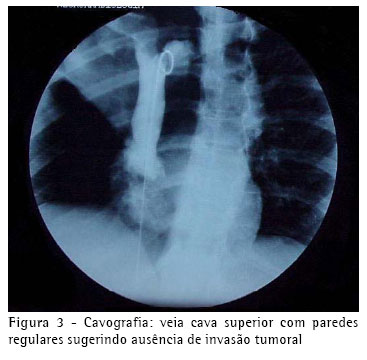

Pela suspeita tomográfica de invasão da veia cava superior e veia ázigos, a investigação prosseguiu através de uma cavografia, que não evidenciou comprometimento destas estruturas (Figura 3).